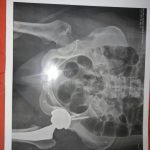

تعویض مفصل زانو و لگن

– شکستگی و در رفتگی

– ساییدگی مفاصل

– از بین رفتن مفاصل